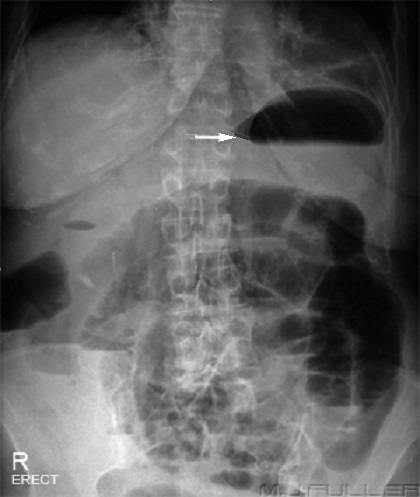

Image distention aerique de

l'estoma surexpose au desus colon transverse

.Ligament gastro colique en vue tres net |

Aspect de l'intestin

grele normale ,en distention aerique legere et

inportant . Cliche ASP de face |